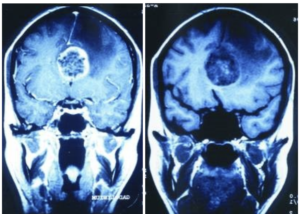

Como era zurda, este conflicto impactó en el lado derecho del cerebro, es decir, en el relé de la insulina. Ella tuvo durante 30 años hiperglucemia, pero no fue diagnosticada con diabetes debido a que no presentaba síntomas (algo muy común). Sin embargo, comenzó a tener algunos síntomas de esta hiperglucemia cuando tuvo que cuidar a su padre postrado los últimos 5 años. Cuando el padre muere, ella resuelve definitivamente y las molestias la llevan al diagnóstico de tumor cerebral, que no es más que la PCL en el relé de la insulina debido a que ha resuelto el conflicto definitivamente (ver foto del final del artículo).